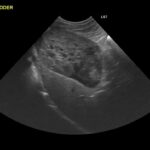

主に血液検査、レントゲン検査、超音波検査(胸部・腹部)を行います。腫瘍が大きすぎたり、隣接する臓器との関係性がわからない場合はCT検査を行います。

最終的な確定診断は病理組織診断となります。

しかし、ほとんどの血管肉腫は出血しやすく止血できなくなる可能性もあるため安易な針吸引検査はしないのが一般的です。

皮膚や、皮下組織にできたものに関しては細胞診を行うことがあります。